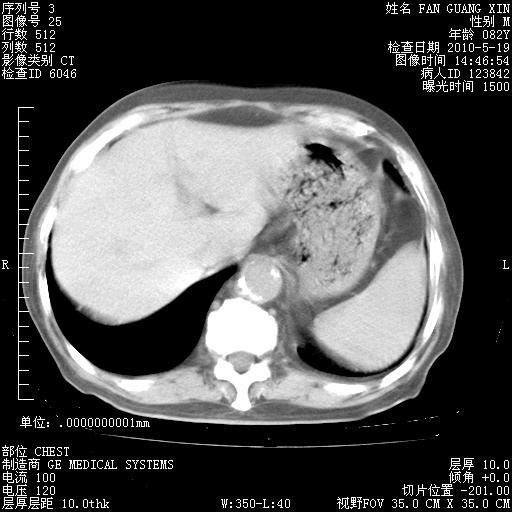

再治疗10天后的肺部CT 纵膈窗

从白细胞总数和中性比例看好像合并感染。肺部纹理好像比上次多,支气管炎?其他感染?

阅读此次胸部CT,肺间质渗出性改变较入院时有吸收。目前从体温、白细胞、中性分叶明显增高,肯定存在细菌感染(发生医院感染哦,若无消化道及泌尿系统等感染的依据,肺部感染可能大)。若你院头孢哌酮舒巴坦钠耐药率较高,同意你的方案,若48小时体温仍高,可考虑使用碳青霉稀类抗菌药物,同时可予超声雾化、注意滴数时加大液体量。白蛋白33.30g/L较低哦,需加强营养等支持治疗。